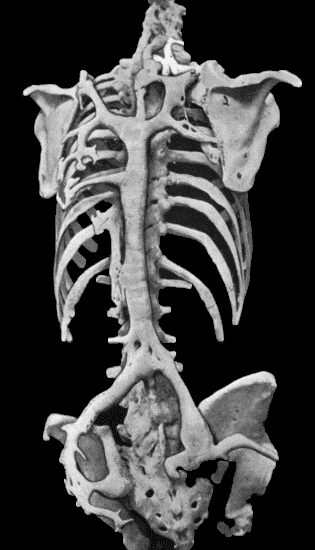

| 112. | Ossification in Muscles of Trunk in generalised Ossifying Myositis | 419 |

| 133. | Skeleton of Rickety Dwarf | 470 |